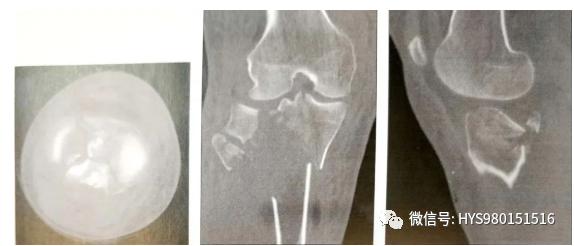

• CT扫描能有效观察关节内骨折情况。标准的扫描应该包括轴位、冠状位和矢状位;

• CT可以提供完整的关节损伤信息,包括髁间嵴骨折,关节面塌陷的位置和程度,骨折块的大小,前交叉韧带撕脱骨折和后交叉韧带胫骨附着点撕脱骨折。

▲ 髁间嵴骨折

▲ 关节面塌陷的位置和程度